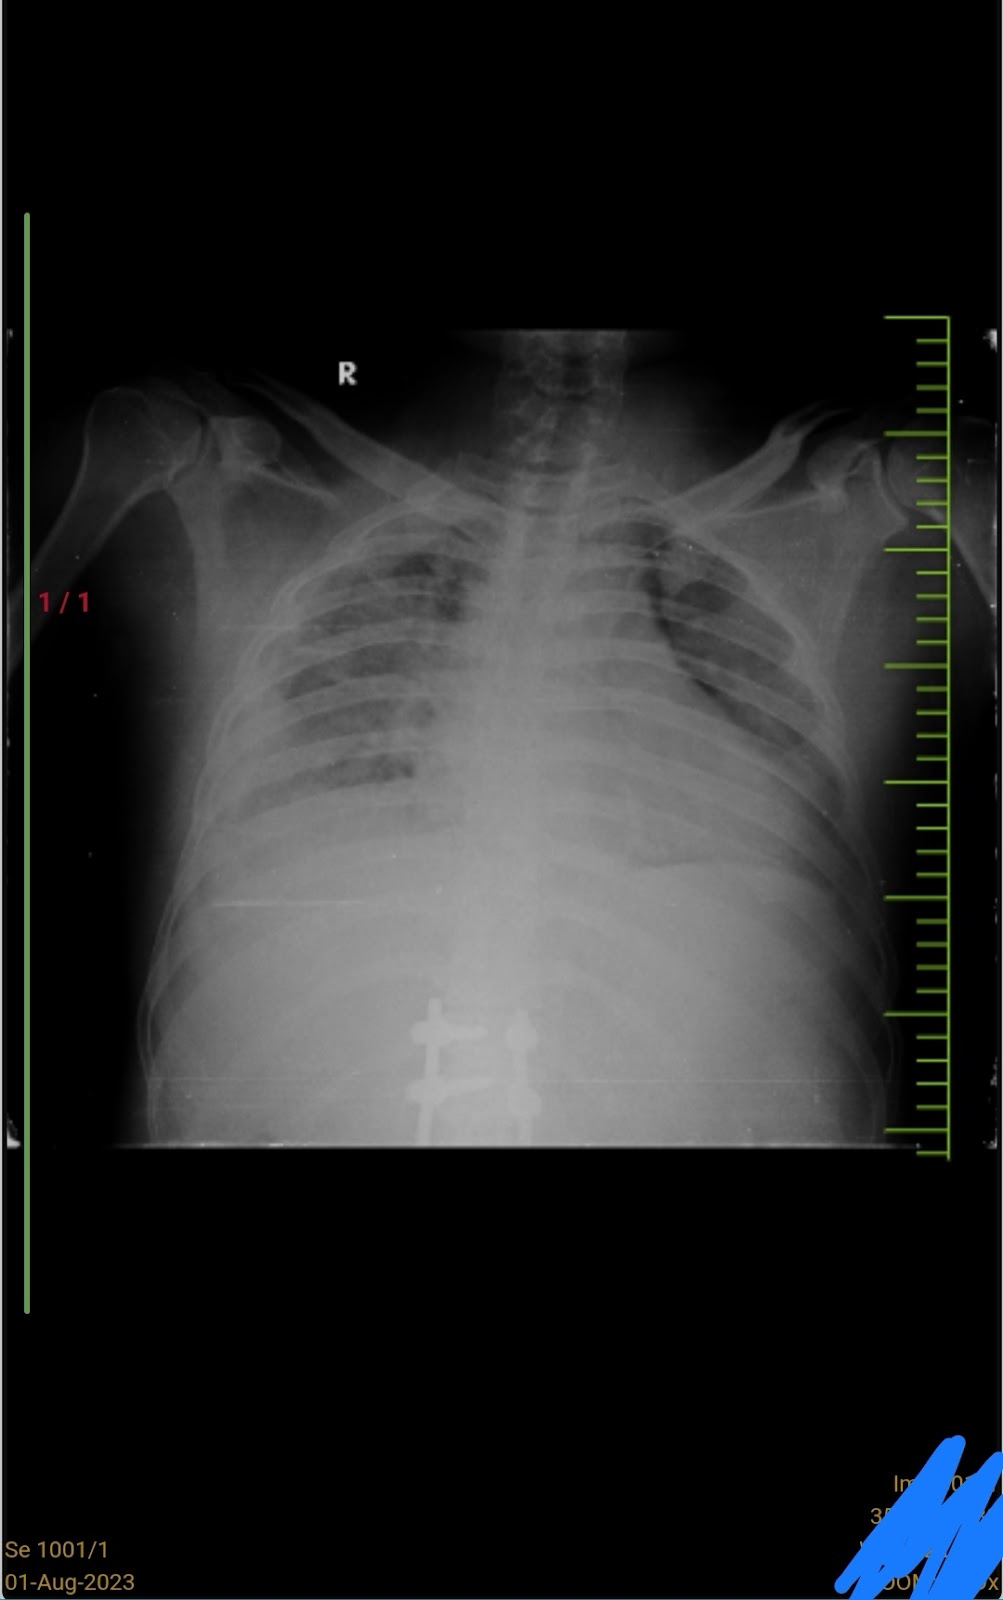

Chest xray On 28/7/23

1/8/23